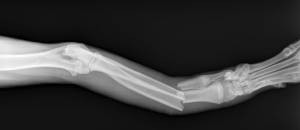

Radiographies pré et post-opératoires d’une fracture radio-ulnaire de chien.

Chiens et chats sont régulièrement victimes d’accidents de la voie publique avec pour conséquences différents types de fractures des membres, du bassin, du dos ou du crâne. Après une période nécessaire de stabilisation des fonctions vitales et de récupération, le passage au bloc opératoire est souvent nécessaire pour retrouver la forme initiale de l’os et entamer le début du processus de guérison.

La chirurgie orthopédique fait aujourd’hui appel à des technologies de plaques et de vis qui réduisent l’inconfort et favorisent une cicatrisation rapide en respectant la physiologie de l’os et des processus biologiques. Le repos, une gestion adéquate de la douleur et une mobilisation douce et adaptée permettent une reprise d’activité d’abord partielle puis souvent quasi complète du membre opéré.